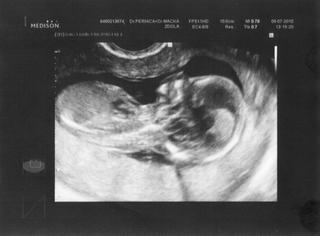

Ovsem me bavi, jak ty potvurky nemaji rady utz, takze jim "skacou". Proste si ho zamerili...a sup, byl v jinym konci delohy 🙂 (oni, protoze tam byl dr. plus vim ja, jestli medik nebo cerstvy mudr., ale ucil se, vysvetloval mu, co kde jak je videt, ev. jak nastelovat, aby videl 🙂)

opravdu je kouzelné jak to malé před doktorem prchá a všemožně se mu snaží vyšetření znemožnit...ale zážitek je to krásný když na vás tahkle z bříška zamává ..mě vždycky tečou slzy jen si na to vzpomenu 🙂